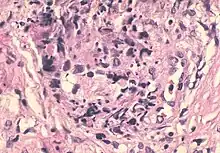

Sperm granulomas are diagnosed using a microscope to examine tissues (histology) taken from the area, typically done with fine needle aspiration and occur within a few weeks of a vasectomy.[7] An example of a histology based diagnosis supporting sperm granuloma would be a sperm core surrounded by inflammatory cells, apoptotic cells, and fibrous tissue. Often, there will be empty tubes with cellular debris near the granuloma.[2] Additionally, physicians might use high frequency ultrasounds to aid in properly diagnosing epididymal conditions such as sperm granulomas.[8] Using these ultrasounds provide a better view of the anatomy of the epididymis, which could prevent misdiagnosis of conditions such as testicular tumors or supernumerary testis (the presence of more than two testes).[8]

Sperm granuloma is a common complication of vasectomy.[2] Vasectomies are a common, effective procedure for the sterilization of males. History of trauma or epididymitis can also lead to sperm granuloma. In vasectomies, the vas deferens are cut and the two ends are tied to prevent sperm from passing. Sperm granuloma may then grow at the point where the vas deferens were cut.[2] This could happen two to three weeks post procedure. Sperm granuloma can also form from sperm leaking from the vas deferens into the surrounding interstitium. Leakage of sperm elicits an immune response which can lead to chronic inflammation. A histological examination can confirm a sperm granuloma by checking for inflammatory markers such as macrophages and lymphocytes surrounding the sperm core.[2]